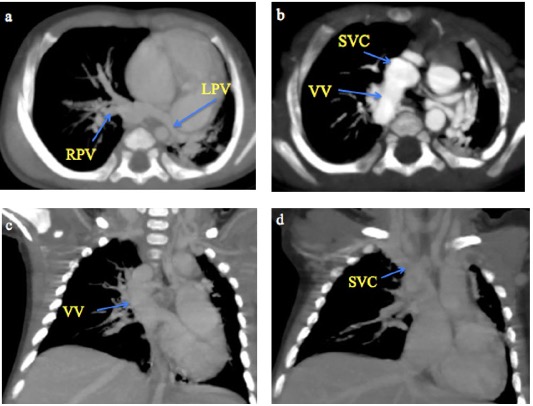

Fig. 4 A 2-month male infant with supracardiac total anomalous pulmonary venous connection. (a-b) CT Pulmonary angiography axial MIP sequential images from caudal to cranial levels showing the left pulmonary veins (LPV) and right pulmonary veins (RPV) converging to form a vertical vein (VV) that drains into the superior vena cava (SVC). (c-d) Coronal MIP images demonstrating the VV draining into the SVC.

TAPVC, in which all four pulmonary veins drain into the systemic veins rather than the left atrium, is usually diagnosed on echocardiography4. However, MDCT angiography is indispensable when echocardiographic visualization is limited or complex CHD is suspected. The supracardiac type of TAPVC was the most common in this study (45.5%), consistent with previous reports (45%-55%)8,10. In our study, MDCT angiography effectively characterised various drainage patterns, including a supracardiac TAPVC draining into the SVC and a rare infracardiac type of TAPVC draining into the splenic vein, also reported by AI Mutari et al26. MDCT’s 3D reconstructions provided crucial details for accurate delineation of venous stenosis.